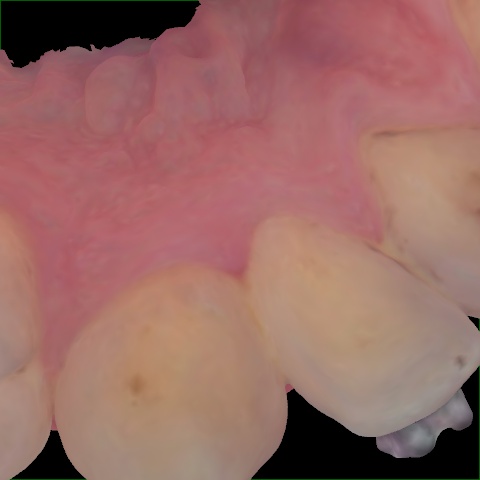

Image 1946 / 2000

NHD39969

Annotated as "Good"

Original Image Rendering Image